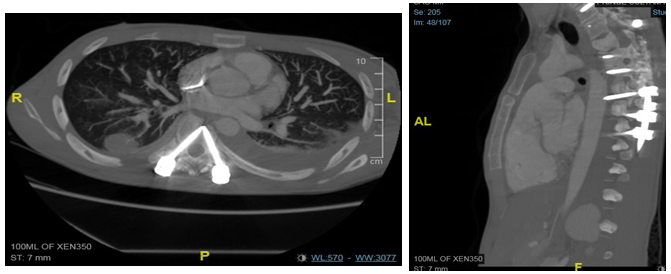

A 26-year-old male, soldier, involved in road traffic accident on 27th of August 2019 in the southern region of Saudi Arabia. The patient was transferred to the military hospital in the south and they stabilized him there and then transferred to our hospital on 29th of August 2019. The patient had multiple injuries: T3–T4 spinal fracture (Figure 1), left proximal humerus fracture (Figure 2), 8th & 9th rib fractures with multiple lacerations. He underwent for left open reduction and internal fixation of the proximal humerus by using Proximal Humerus Internal Locking System "PHILOS" plating on 03-Sep-2019 (Figure 3A & 3B). Also, the patient underwent spinal fixation for the fracture from T1 to T8on 05-Sep-2019 (Figure 3C). One month postoperatively, he started to have left big toe gangrene and vascular surgery was consulted. They recommended doing CT angiogram of the aortic arch and echocardiogram. CT showed that left pedicular screw of T6 and T8 appear lateral to the pedicle and the tip of the screws abutting the medial wall of the descending thoracic aorta at the posterior mediastinum but there is no obvious surrounding active haematoma or aortic thrombosis (Figure 4A & 4B). Pre-operative assessment and measurement were done and it was showed: Whole length supposed to be covered: 10cm, Proximal landing zone on the sagittal view: 2.67cm, Distal landing zone on the sagittal view: 1.83cm, Proximal axial: 2.14cm x 2.11cm, and distal axial: 1.92cm x 1.78cm.

Figure 4 CT Axial cut (A) and Sagittal cut (B) showed The thoracic aorta appears intact however the left pedicular screw of T6 and T8 appear lateral to the pedicle and the tip of the screws abutting the medial wall of the descending thoracic aorta at the posterior mediastinum but there is no obvious surrounding active haematoma or aortic thrombosis. Whole length supposed to be covered: 10cm, Proximal landing zone on the sagittal view: 2.67cm, Distal landing zone on the sagittal view: 1.83cm, Proximal axial: 2.14cm x 2.11cm, and distal axial: 1.92cm x1.78cm.